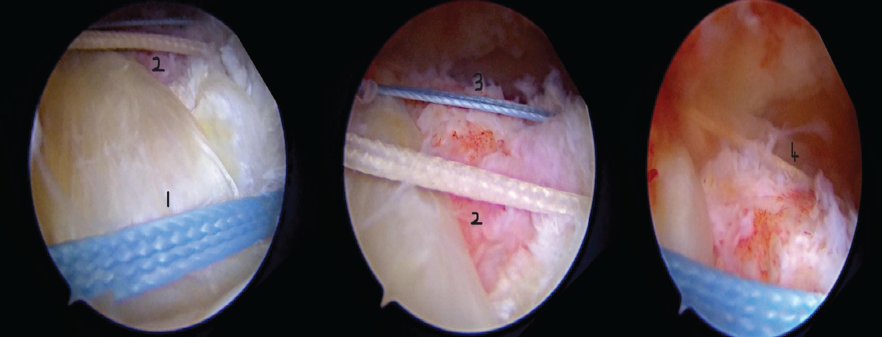

This loop is then used to pass the definitive sutures, which are strategically arranged to create a strong construct for tendon reattachment. For cost-effectiveness, one FiberWire and one FiberTape are bifurcated, yielding four individual strands. Hence, in total, we now have two FiberTapes and two FiberWires in the tunnel [7,8]. Using the FirstPass device, four distinct bites are taken in succession through the cuff tissue to ensure broad and secure fixation [7]. From the far lateral portal, a knot pusher is then meticulously employed to shuttle each suture end into the joint, after which the sutures are retrieved through the lateral portal. Each suture is then tied sequentially using SMC sliding knots, ensuring that the thread(FiberWire/FiberTape) exiting inferiorly is maintained as the post for the SMC sliding knot so that the knot will be at the lower tunnel exit, preventing any subacromial knot impingement. The final FiberWire configuration distinctly resembles an inverted “J,” thereby securely reapproximating the rotator cuff to its anatomical footprint and completing the fixation [1,6,9,10] (Fig. 5 and 6).

Figure 5: Final repair.

Figure 6: Illustration showing inverted J configuration of suture.